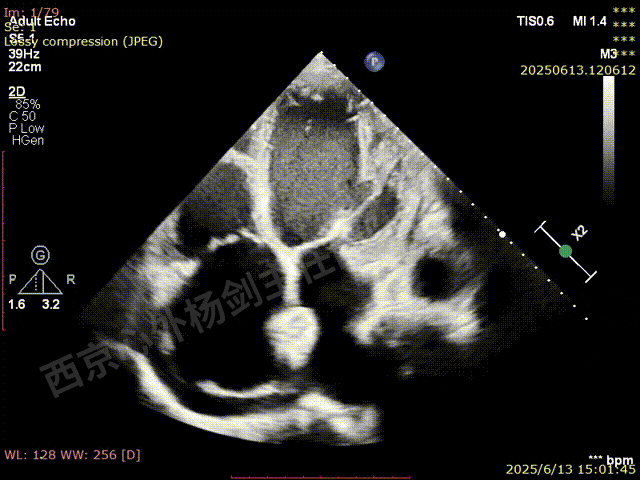

TAVR术后,全心增大,二尖瓣反流重度,三尖瓣反流重度。中量心包积液。左室严重增大,标准图像调整困难。主动脉瓣位带支架人工瓣膜瓣叶启闭正常,主动脉瓣位人工瓣上血流速度Vmax 148cm/s,PGmax 9mmHg,Vmean 86cm/s,PGmean 2mmHg, VTI 34.7cm,瓣周反流(轻)。估测肺动脉收缩压约49mmHg;左室收缩功能明显减低。LVEF:23%,EDV:364ml,ESV:221ml。

彩色血流示:二尖瓣反流缩流颈彩宽6.6mm,面积17cm²,容积30ml;二尖瓣瓣口面积6.6cm²,瓣环内径:左右径34mm,前后径34mm。2区瓣叶长度:前叶36mm,后叶20mm,叶环比1.6. 三尖反流面积17.2cm²,容积33ml,Vmax 291cm/s,PGmax 34mmHg。